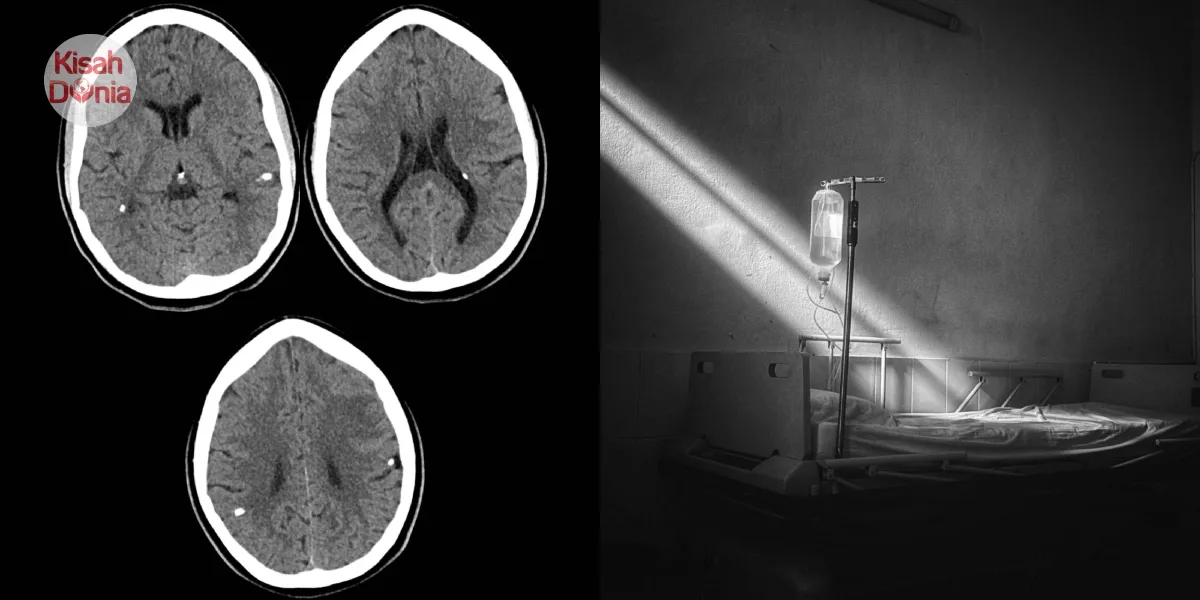

Selepas disahkan positif HIV & Toksoensefalitis, dia nangis meraung-raung

Di sebalik gaji yang lumayan, dia bagaimanapun disahkan menghidap Toksoensefalitis (bisul/keradangan otak) serta jangkitan kelamin. Sepanjang dirawat di hospital, lelaki itu benar-benar menyesal dengan jalan hidup yang dipilihnya dan dilihat sentiasa membaca Al-Quran. Tidak lama kemudian, dia akhirnya kembali kepada Sang Pencipta.